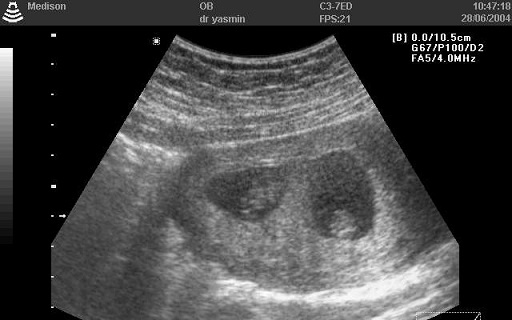

Elviselhetetlen hátfájásra panaszkodott kétórás edzése után egy amerikai futónő, aki épp a félmaratoni táv teljesítésére készült. Kiderült, hogy fájdalmainak oka nem sérülés, hanem terhesség: az edzés másnapján, június 3-án újszülöttet tarthatott a karjában.

A 33 éves Trish Staine azt mondta, hogy a hétfői "meglepetés" szülésig fogalma sem volt arról, hogy terhes. A háromgyermekes duluth-i anya állította, hogy nem hízott és magzatmozgást sem érzett az előző hónapokban. Férje ráadásul meddővé tevő műtéten, vazektómián esett át.

A kórházi vizsgálaton férjével együtt meglepődtek, amikor az orvosok magzati szívhangot találtak. Az anyát azonnal a szülőszobába szállították, ahol kislánynak adott életet. Az orvosok szerint a baba a várhatónál öt héttel korábban született, 2900 grammos súllyal és 48 centiméterrel.